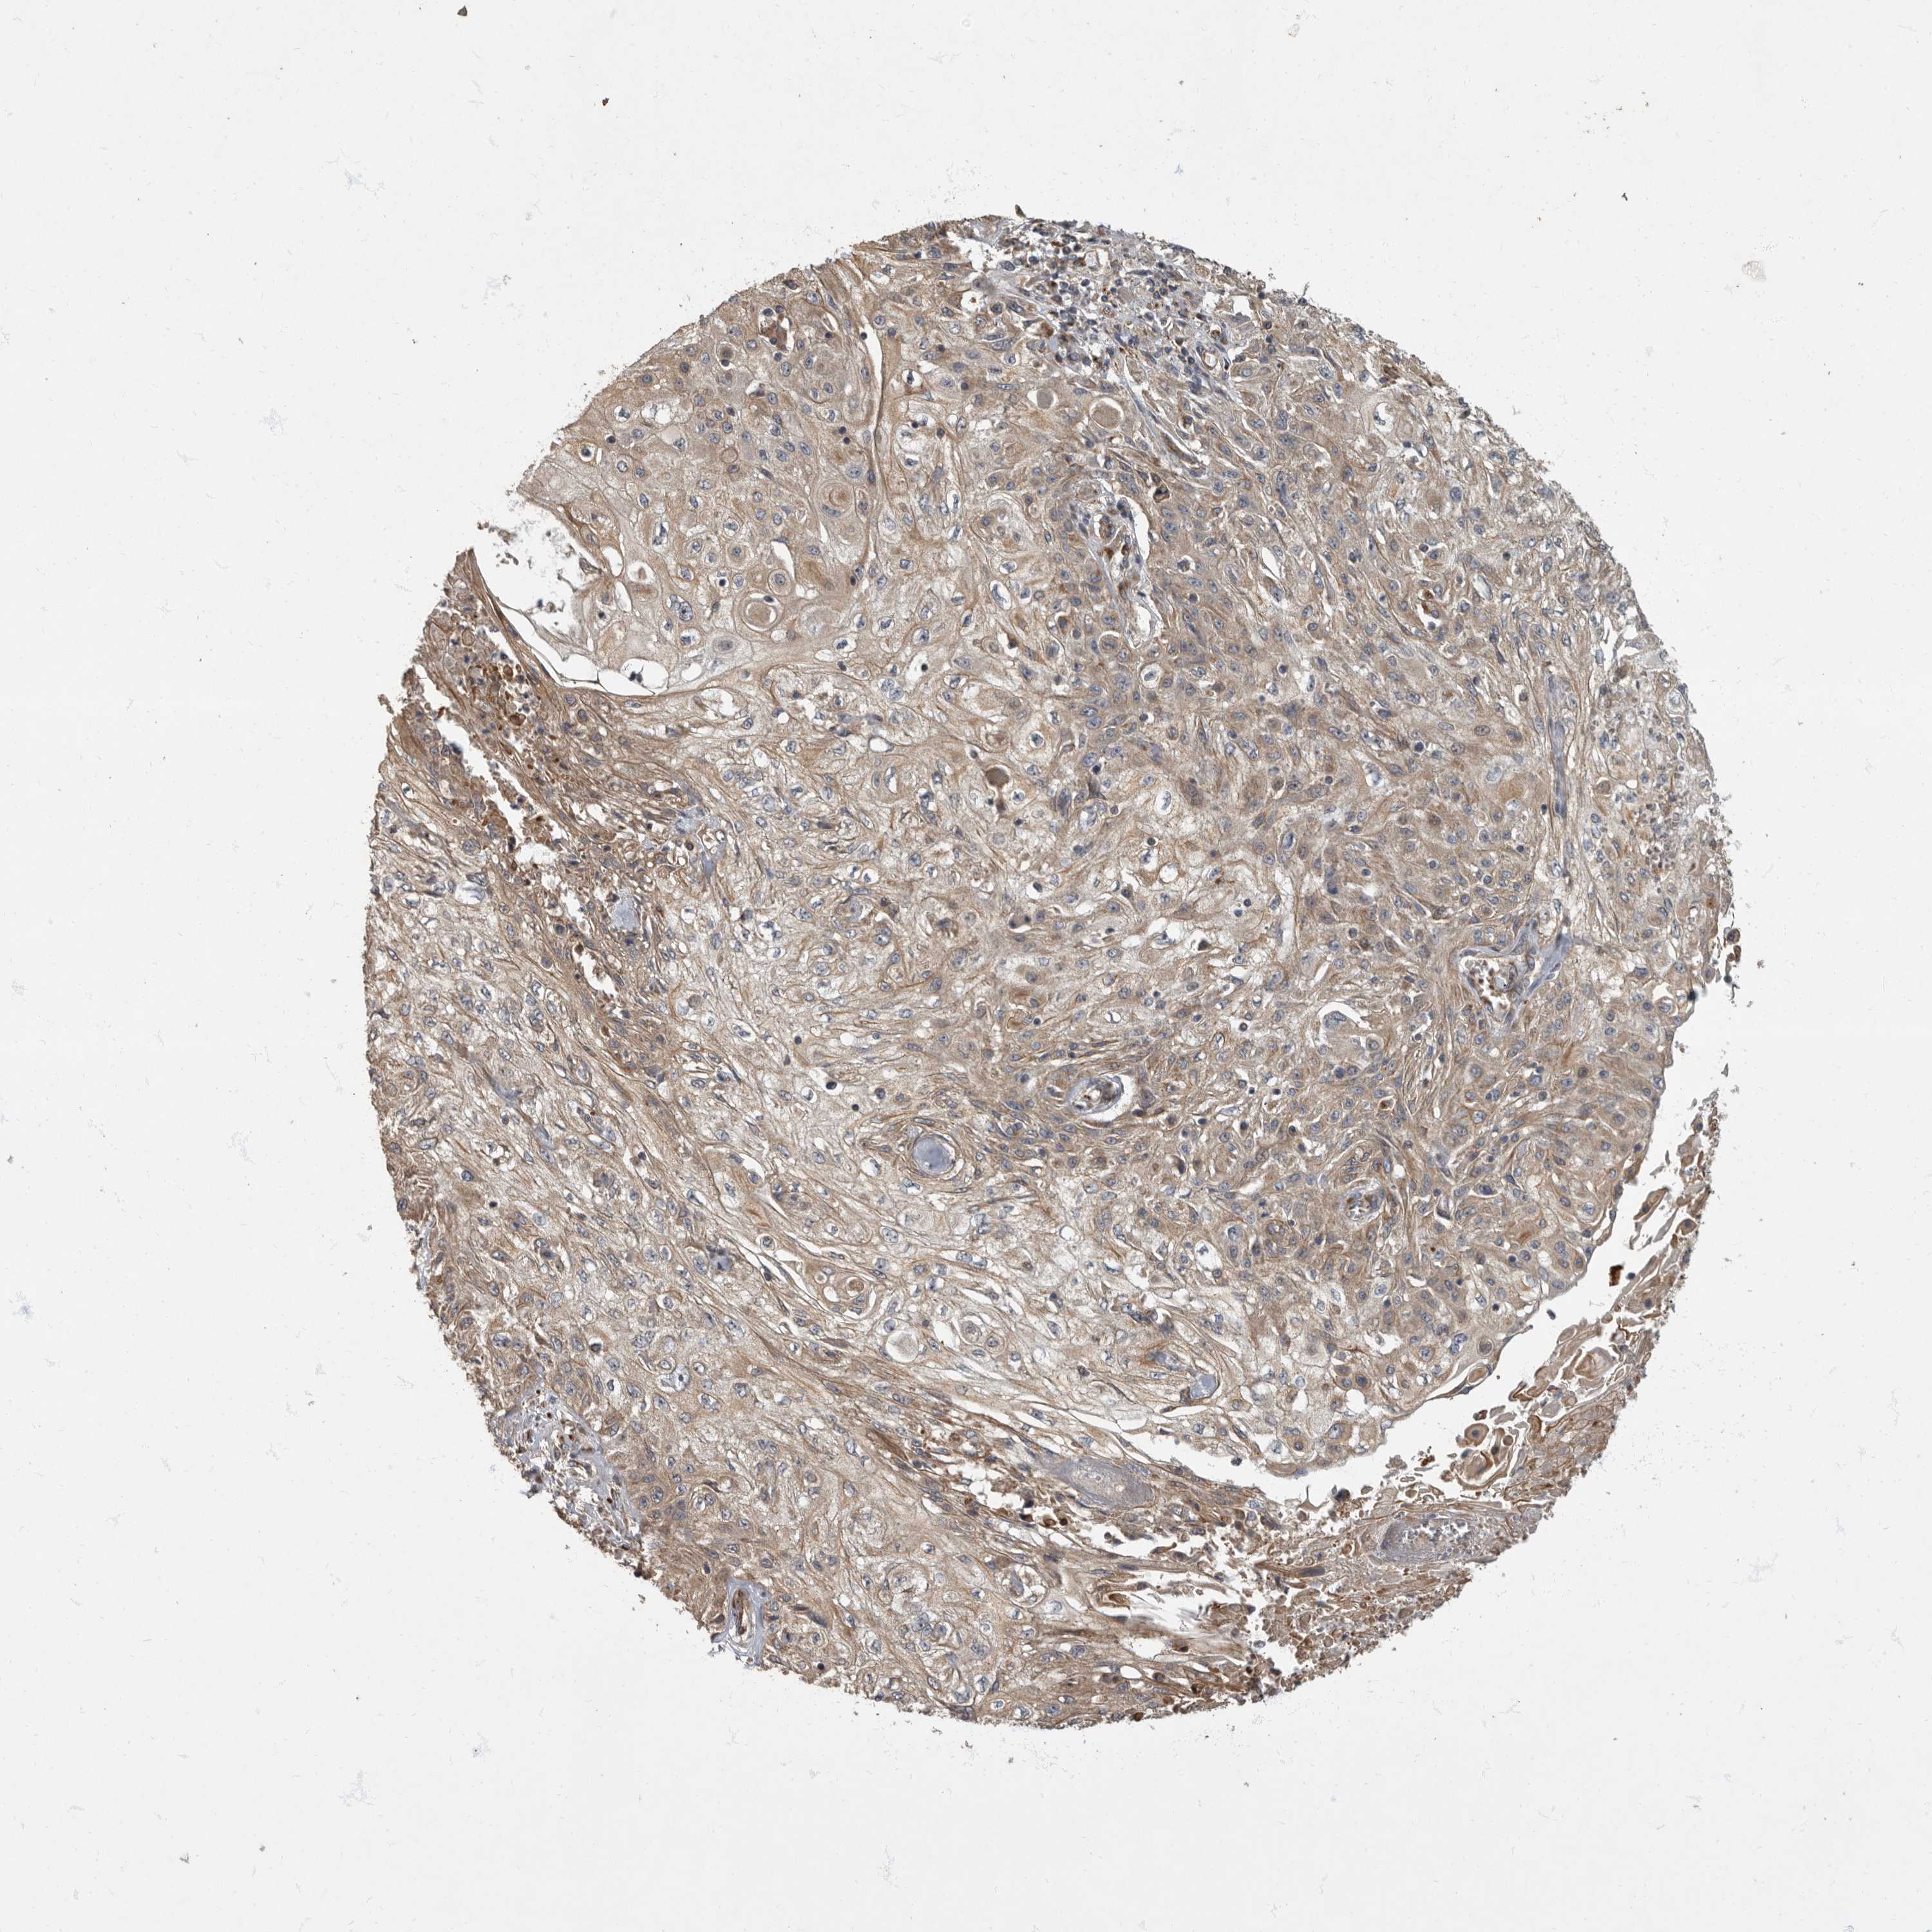

Basal cell and squamous cell cancer

SKIN CANCER - Protein expressioni

A mouse-over function shows sample information and annotation data. Click on an image to view it in a full screen mode. Samples can be filtered based on level of antibody staining by selecting one or several of the following categories: high, medium, low and not detected. The assay and annotation is described here.

Antibody stainingi

Antibody staining in the annotated cell types in the current human tissue is reported as not detected, low, medium, or high, based on conventional immunohistochemistry profiling in selected tissues. This score is based on the combination of the staining intensity and fraction of stained cells.

Each image is clickable and will lead to virtual microscopy that enables deeper exploration of all samples and also displays staining intensity scores, fraction scores and subcellular localization as well as patient and tissue information for each sample.

Antibody HPA026792

Staining

Squamous cell carcinoma, NOS

Squamous cell carcinoma, metastatic, NOS